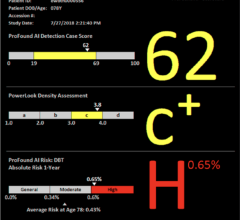

The prestigious Joint AAPM Task Group 282/EFOMP Working Group, focused on modernizing breast radiation dose modeling, recently published a report outlining their new model in Medical Physics. The report, "Breast dosimetry for standard and contrast-enhanced mammography and breast tomosynthesis," advocates for international harmonization of mammography dose estimates, by implementation of the new and improved model and methodology. The new model replaces assumptions of a homogeneous breast with a more representative fibroglandular tissue distribution and shifts to the use of percentage volumetric breast density (%VBD) to align with a clinically implemented breast composition metric. Volumetric breast density emerges as an essential input to facilitate patient-based radiation dose estimates. Volpara's TruDensity algorithm provides reliable estimates of %VBD from 2D and 3D images across multiple mammography system makes and models.

This new dose model will be integrated into Volpara's TruRadDose algorithm, which analyzes a patient's exposure to radiation from a mammogram, with the aim of ensuring patient safety while maintaining optimal image quality.

Featured in European Radiology, a second peer-reviewed study investigates whether active use of Volpara Analytics software could help breast radiographers to improve their screening image quality. The paper "Using automated software evaluation to improve the performance of breast radiographers in tomosynthesis screening," reports on analysis of a quality improvement project where radiographers and researchers from the Breast Radiology Unit at the Veneto Institute of Oncology, encouraged active use of Analytics and led monthly face-to-face coaching sessions with each of six participating radiographers to review individualized feedback based on the objective breast compression and positioning quality metrics measured by Volpara's TruPressure and TruPGMI AI algorithms. All radiographers improved their performance, with increases in quality scores of up to 16% compared to a baseline measurement. The study concluded that employing Volpara's AI-driven software significantly enhances radiographers' performance, thereby improving mammography quality and potentially leading to better screening outcomes for patients. The study's lead author, Gisella Gennaro, notes that a key aspect of the project was to determine whether use of Volpara Analytics software by even the most senior radiographers, would be both accepted and beneficial. She comments that the quality of "all radiographers benefited from the personalized learning experience, with consistent and objective measurements that can be benchmarked against peers."